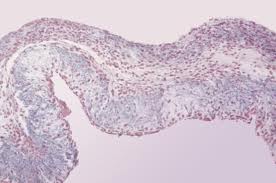

Общие сведения Эндокардит, воспалительное заболевание внутренней оболочки сердца, может быть одним из проявлений ревматизма, а может быть и самостоятельным заболеванием инфекционной природы. Сейчас мы рассмотрим причины и главные симптомы инфекционного эндокардита (ИЭ), а так же методы его диагностики и лечения. Этиология и пути заражения Возбудителями эндокардита являются чаще всего такие микроорганизмы как стрептококки, стафилококки, энтерококки, […]